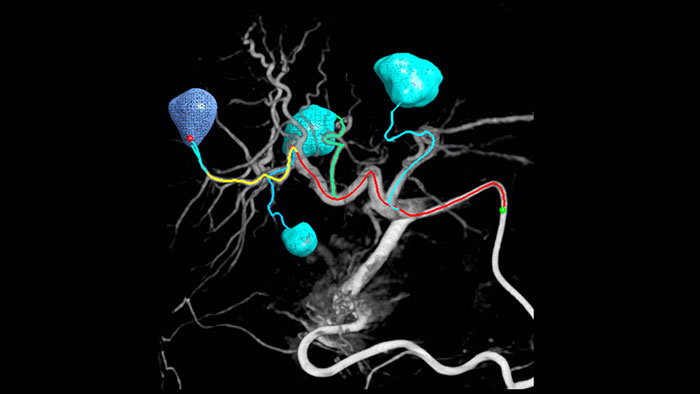

Появление таких методов химио- и радиоэмболизации, как трансартериальная химиоэмболизация (ТАХЭ) и селективная внутренняя радиационная терапия (SIRT) указывает на потребность в стандартизации и повышении эффективности терапии. Для каждого пациента необходимо точно и быстро определить местоположение опухоли, все питающие сосуды, а также спланировать и выполнить необходимые хирургические процедуры. Инструмент для автоматического обнаружения питающих артерий способствует лучшему обнаружению соответствующей артерии в сравнении с использованием только КТ-подобных изображений. EmboGuide помогает достичь максимальной эффективности процедур трансартериальной химиоэмболизации (ТАХЭ), способствуя повышению чувствительности, снижая число ложноположительных результатов и обеспечивая максимальную согласованность считывания показателей несколькими специалистами1.

Возможность обнаружения и дифференциации узелков в печени и определения крошечных питающих сосудов играет важнейшую роль при выборе правильного лечения. Продвижение к исследуемой области с проработкой всех питающих сосудов вкупе с избирательностью обработки области поражения увеличивает шансы на успех. Возможность проверки исхода проведенной процедуры в момент нахождения пациента на столе повышает уверенность в клинических результатах.